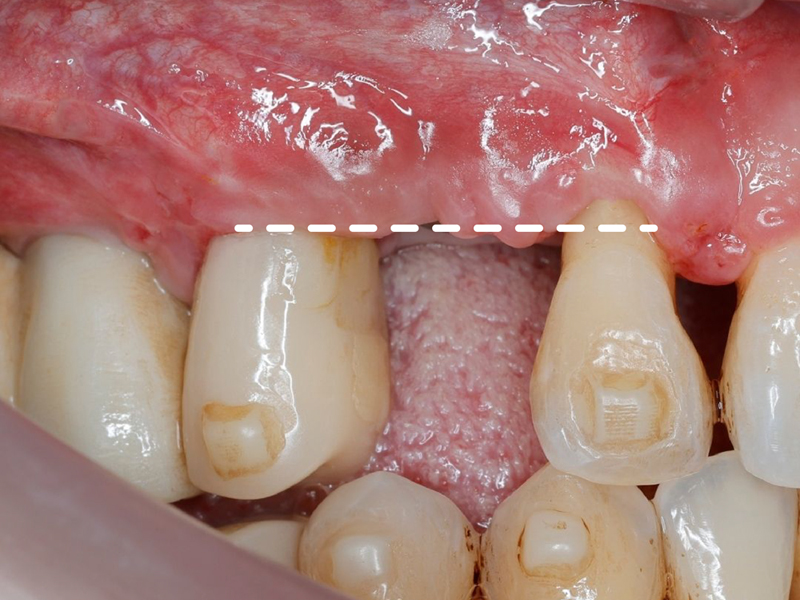

高效補骨 首頁 美麗見證 高效補骨 補骨不可怕,植牙失敗才可怕! 兆品美學牙醫用案例告訴你!植牙就像蓋房子,地基穩不穩固很重要 More 為什麼需要補骨,不能直接植牙呢? 造成骨量不夠的原因通常是缺牙時間過長、牙周病、年齡老化⋯⋯ More «1»